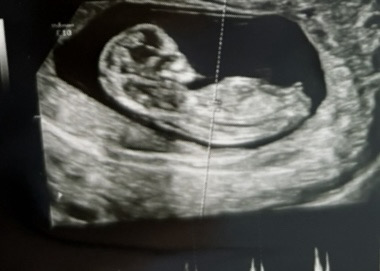

섰..섰구나 아들

2026년 3월 베동

11주 각도법 봐주세용 ㅠㅠ

각도법 한번 봐주세여 11주

음 아들같아요 ..!